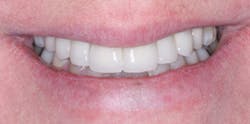

Recently, dentists and laboratory technologists have asked themselves why they were making separate abutments when many clinical situations allow use of a three-piece combination (implant, crown, and a screw through the crown into the implant) without a separate abutment. (Figs. 1-3)

FIG. 1 -- Porcelain-fused-to-metal crown to be screwed directly to implant.

FIG. 2 -- Crown on working cast. Note screw to be placed in hole through crown. Some patients object to the discoloration of the occlusal surface caused by the screw hole. Suggestions on how to restore the hole are included in this article.

This article discusses why the three-piece concept is often better than the four-piece, when it cannot be used, how best to hide the esthetically unacceptable hole necessary for screw access, and what to do when the screw comes loose from the two-piece implant crown combination.

Observe the implant abutments in Fig. 4. The three in the posterior area have had separate abutments placed on them, each with a screw holding the abutment in place on the implant. That technique was not necessary. The implants are approximately in the center of the crowns to be placed over them, and they are nearly perpendicular to what will become the occlusal plane. They could easily have had crowns screwed directly to the implants without a separate abutment. When observing the central incisor with an unaltered manufacturer-made abutment, it is apparent that the abutment is too far facial and will require significant reduction to allow proper thickness of the porcelain-fused-to-metal crown to be placed. Because of this usual bone anatomy angulation in the anterior maxilla, the central incisor is a candidate for a custom abutment, and a four-piece restoration with the crown cemented to the separate abutment.